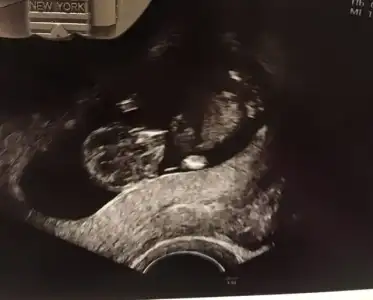

Banada yorum yapabilcek varmı 12+2 yiz

• 3C3F44E1-A8F4-4185-9B12-E8736FAA0EE4.webp

3C3F44E1-A8F4-4185-9B12-E8736FAA0EE4.webp

20,8 KB · Görüntüleme: 59